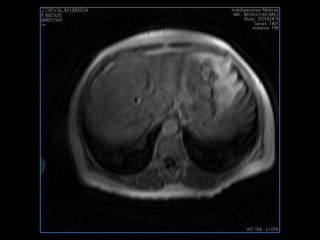

PROTOCOLO hígado graso AXIAL in phase y out phase AX T1 y AX fat sat +SAG T2  CON   GADOLINIO :  COR T1+AX T1(DIN) SAT: NO  FASE: RL THK: 4MM  COIL:  GAP: (FACTOR 1.4)  FOV: 40 CM NEX:2 SINCRONIZACION RESPIRATORIA EN 3 O 4 CICLOS ALE

PROTOCOLO hemocromatosis AXIAL supresión grasa /AX multieco en higado COR T2 AX T1 +SAG T2  CON   GADOLINIO :  COR T1+AX T1 SAT: NO  FASE: RL THK: 4MM  COIL:  GAP: (FACTOR 1.4) 1MM FOV: 40 CM NEX:2 SINCRONIZACION RESPIRATORIA EN 3 O 4 CICLOS ALE

resonancia de abdomen